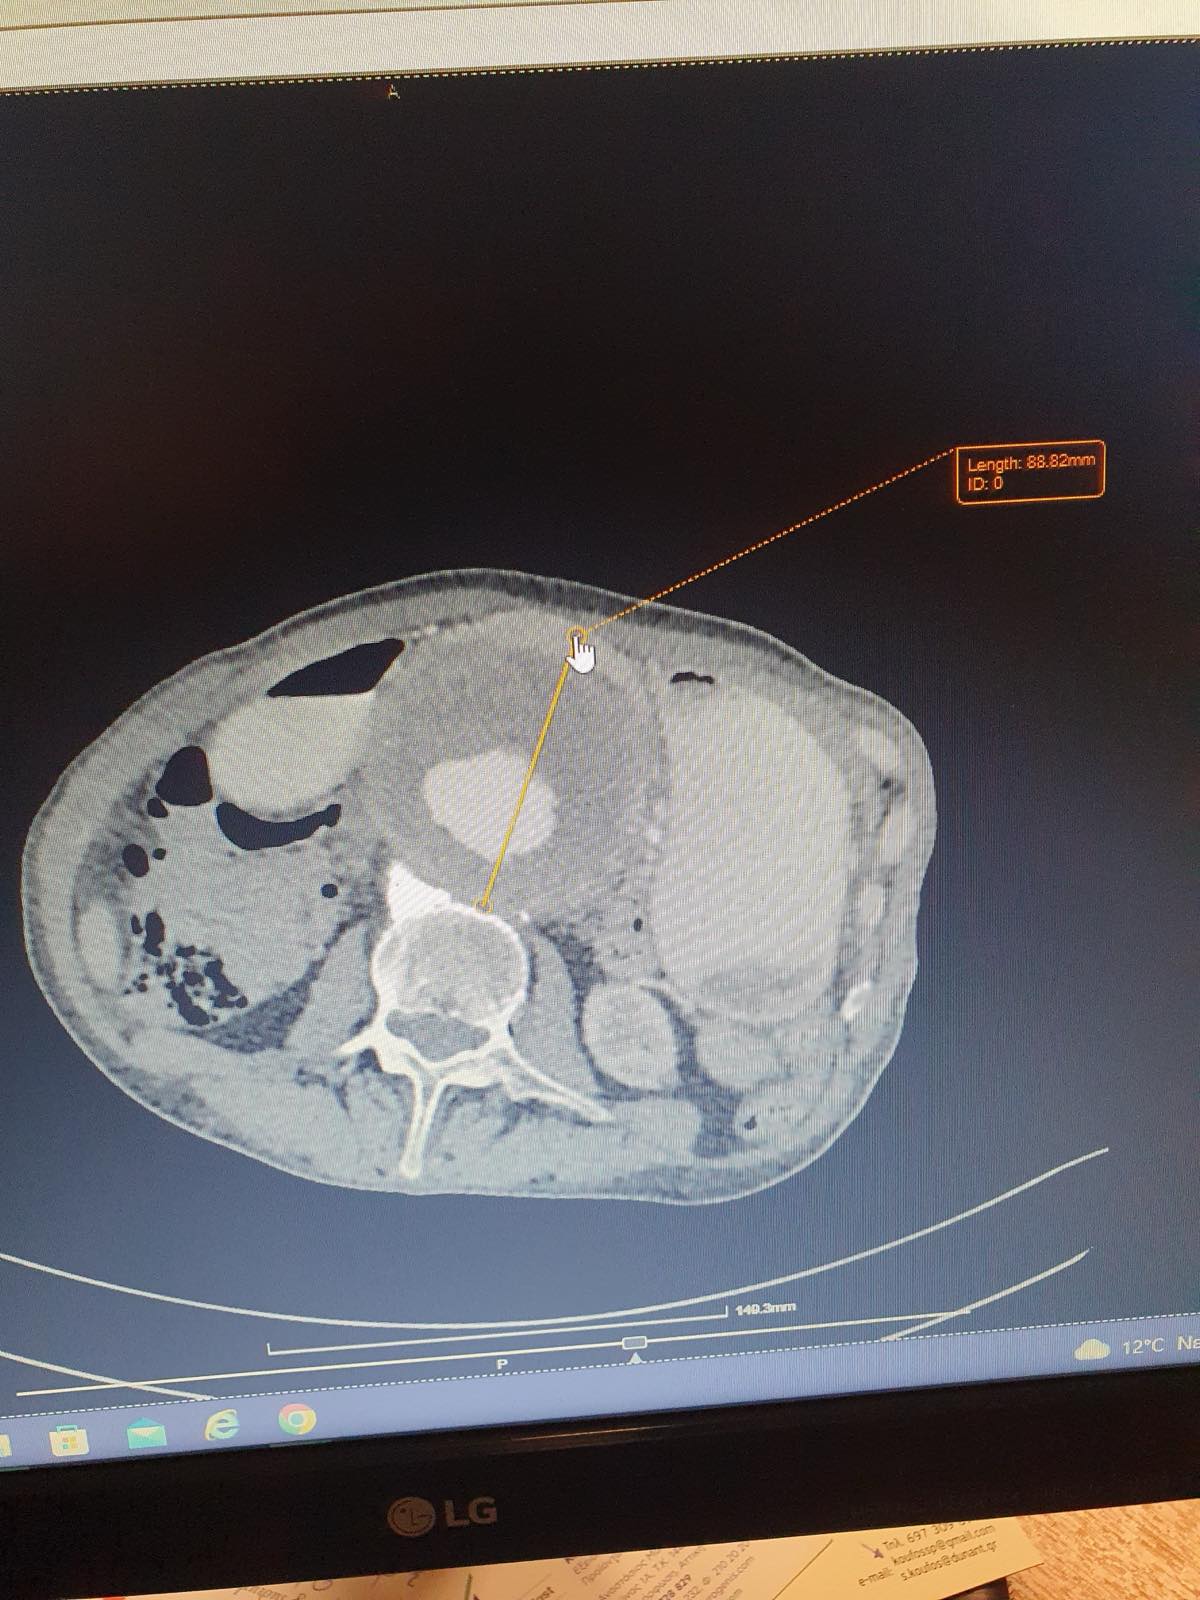

Η διάγνωση του ανευρύσματος κοιλιακής αορτής γίνεται με triplex κοιλιακής αορτής ή αξονική τομογραφία κοιλίας. Κάθε άνθρωπος (στο πλείστο των περιπτώσεων άνδρας) που υπερβαίνει το 60ο έτος της ηλικίας του πρέπει να ελέγχεται με triplex κοιλιακής αορτής (εάν έχει 1ου βαθμού συγγενή με ανεύρυσμα κοιλιακής αορτής η εξέταση πρέπει να γίνει μετά το 50ο έτος). Σε ασθενείς που χρειάζονται αποκατάσταση του ανευρύσματος κοιλιακής αορτής η πιο λεπτομερή προεγχειρητική εξέταση είναι η αξονική αγγειογραφία κοιλιακής αορτής και λαγονίων. Σε ασθενείς που δεν μπορούν να υποβληθούν σε αξονική αγγειογραφία διενεργείται μαγνητική αγγειογραφία κοιλιακής αορτής και λαγονίων.

Η αορτή είναι το μεγαλύτερο αγγείο στο σώμα και μεταφέρει το αίμα από την καρδιά στα υπόλοιπα όργανά. Ως ανεύρυσμα ορίζεται η εστιακή διάταση μιας αρτηρίας τουλάχιστον άνω του 50% της φυσιολογικής διαμέτρου του αγγείου. Επομένως οποιαδήποτε αύξηση της διαμέτρου της κοιλιακής αορτής πάνω από 3 εκατοστά ορίζεται ωςανεύρυσμα κοιλιακής αορτής.

Εάν ένα ανεύρυσμα κοιλιακής αορτής έχει διάμετρο μικρότερη από 5 εκ., έχει μικρή πιθανότητα να υποστεί ρήξη, γι’ αυτό συνιστάται η τακτική παρακολούθηση του ανευρύσματος από αγγειοχειρουργό. Εάν, ωστόσο, ένα ανεύρυσμα είναι μικρότερο από 5 εκατοστά, αλλά αυξάνεται κατά περισσότερο από 1 εκατοστό κάθε χρόνο ή προκαλεί συμπτώματα όπως πόνο στην πλάτη και ευαισθησία, συνίσταται άμεση αποκατάσταση. Εάν το ανεύρυσμά είναι μεγαλύτερο από 5 εκ., θα χρειαστεί αποκατάσταση για την αποτροπή της ρήξης του ανευρύσματος. Η EVAR είναι μια πιθανή θεραπευτική επιλογή.